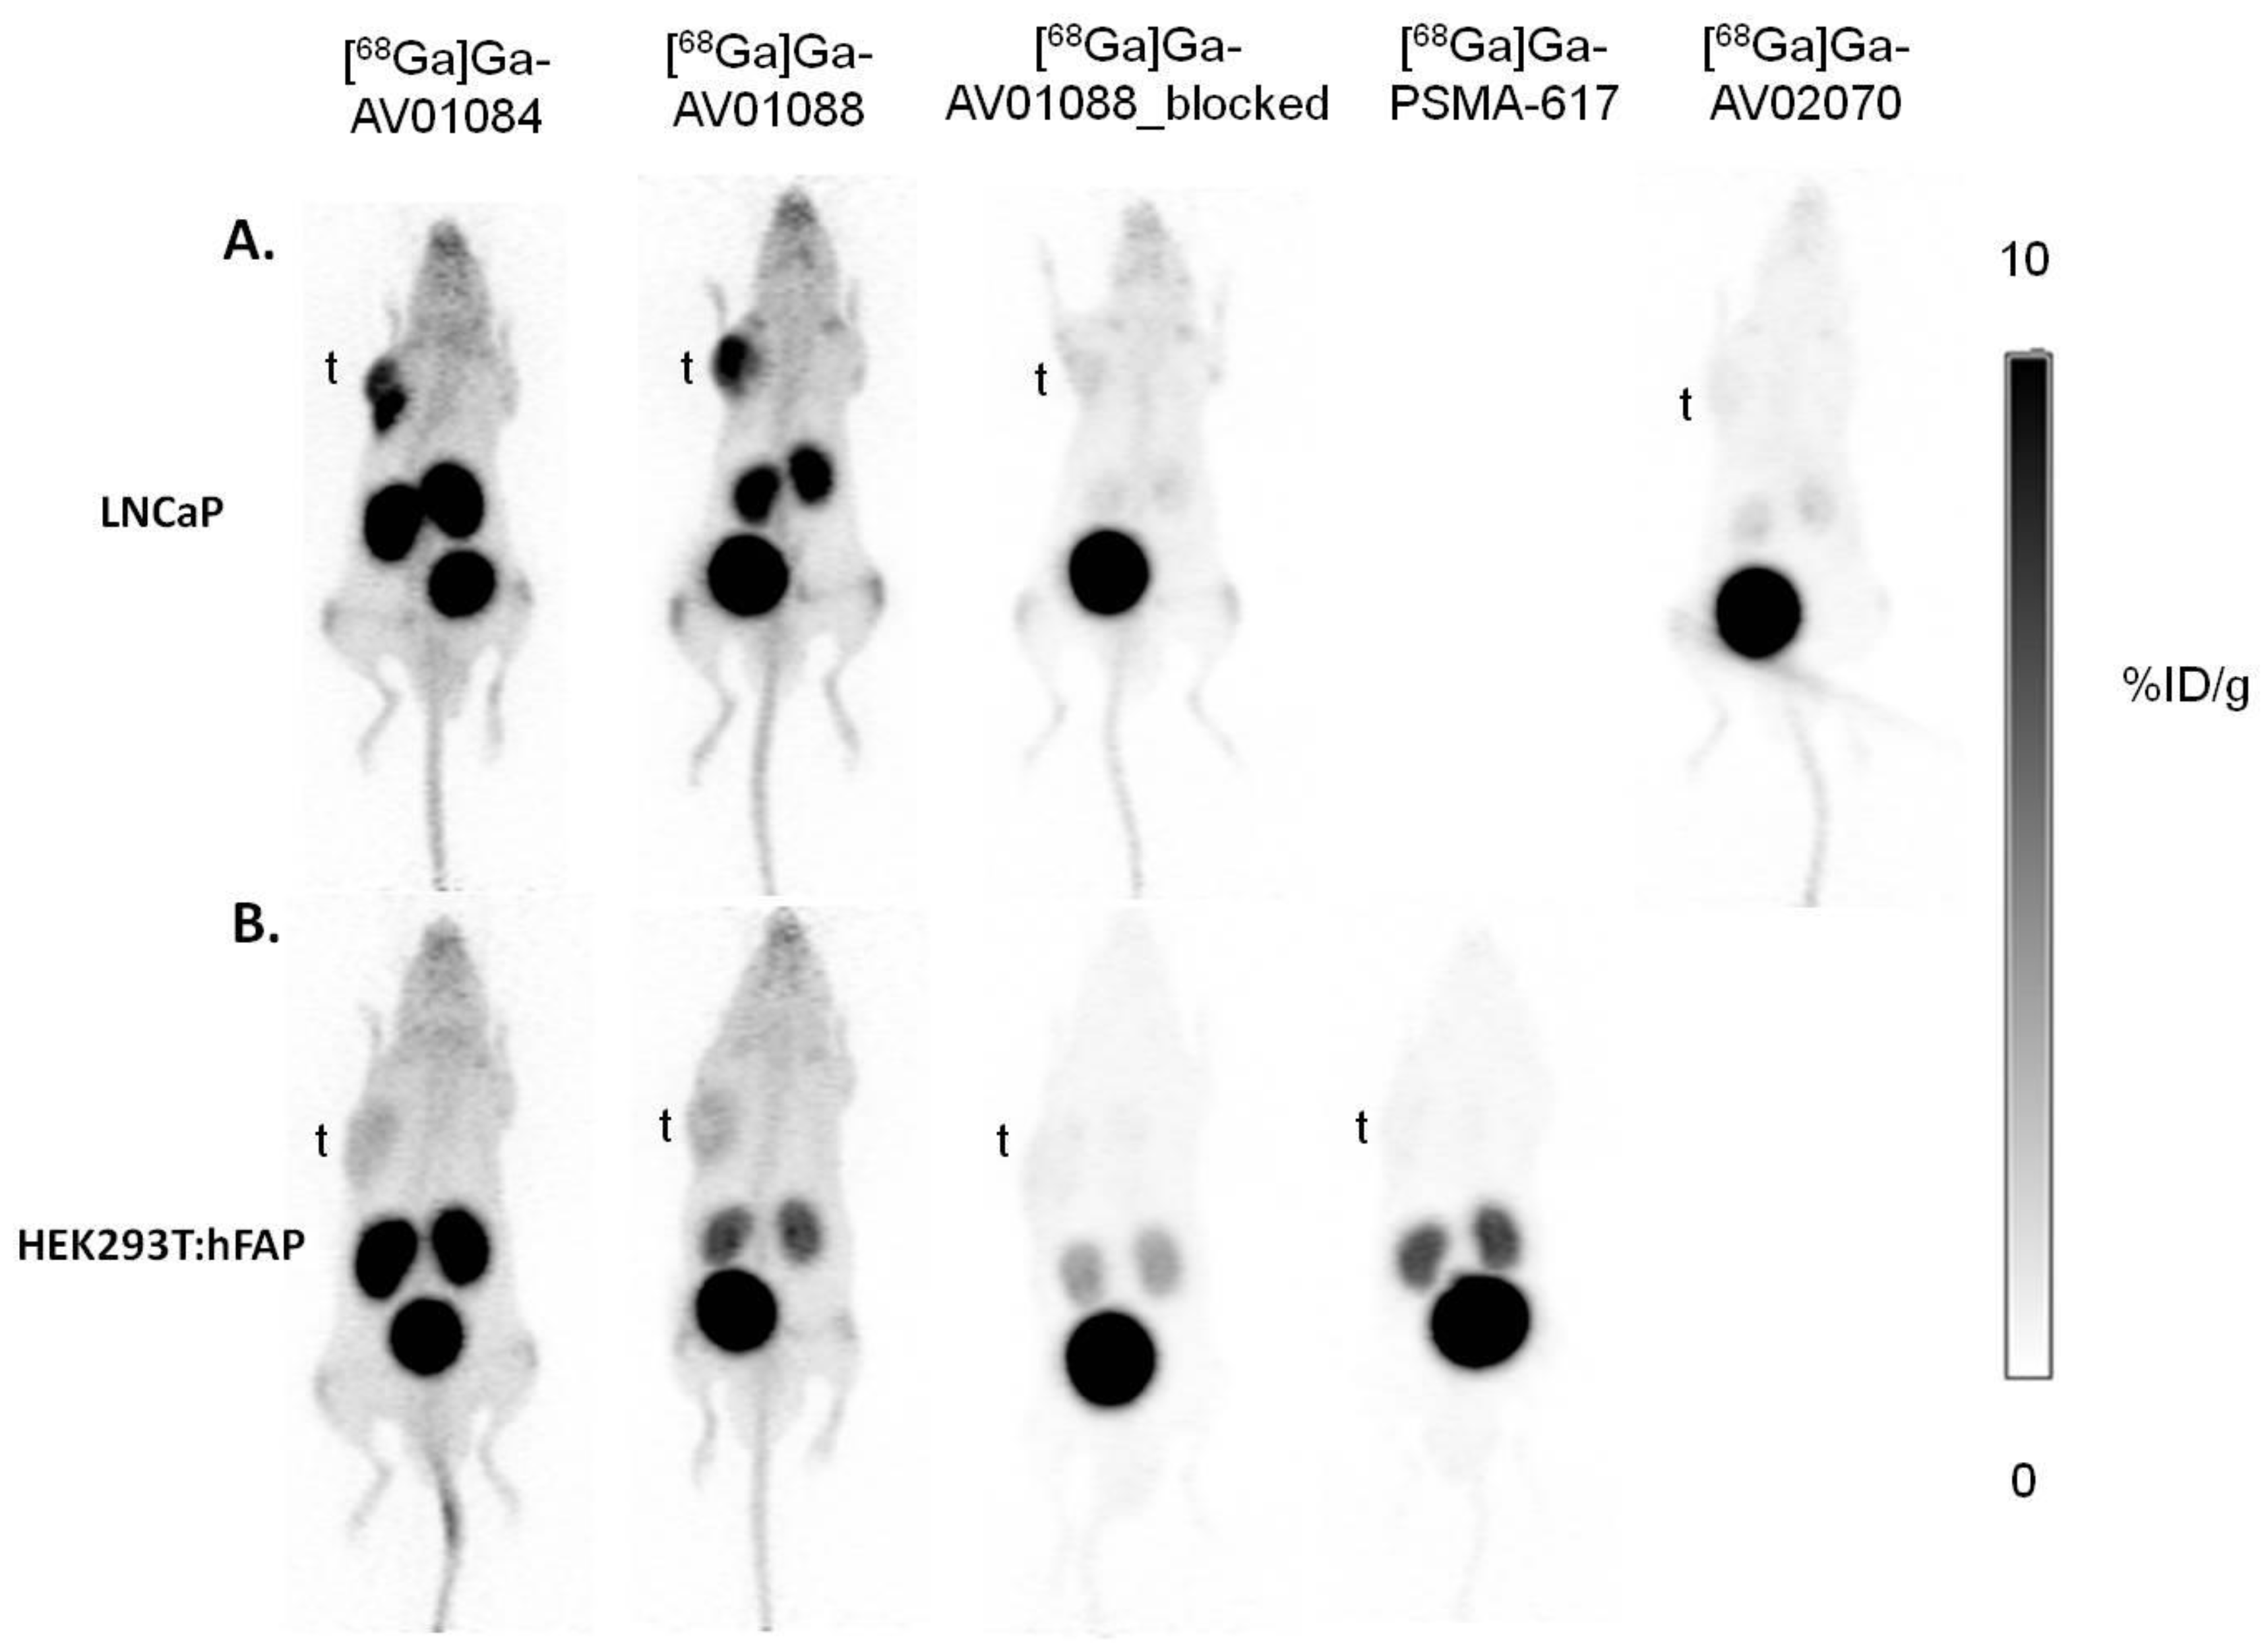

2.3. PET Imaging, Ex Vivo Biodistribution, and Blocking Studies